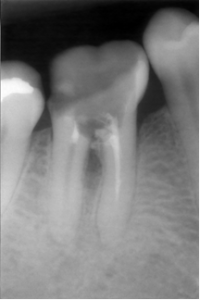

Perforation du placher pulpaire et faux canal.

Perforation du plancher pulpaire et faux canal.